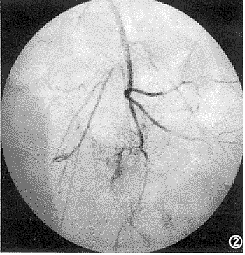

B组15例动脉灌注治疗后,其中3例疼痛消失,12例疼痛缓解或明显缓解,13例局部肿块不同程度变软,14例根治术前(动脉灌注治疗1周后)CT扫描显示肿块边界较治疗前清晰,肿瘤周围水肿减轻或消失。根治中可见多数肿瘤有假包膜形成,肿瘤内部可见大量坏死,肿瘤破坏比率达60%~90%者5例,达40%~60%者6例,余为40%以下。根治术后(二次动脉灌注中)血管造影所示未见局部肿瘤复发血管(图1、2)。

图1 治疗前胫骨上端骨肉瘤病变,造影显示肿瘤血管丰富,肿瘤染色明显 图2 同图1病例。经一次介入治疗后肿瘤明显缩小,造影显示肿瘤血管基本消失,证实肿瘤坏死率可达90%以上